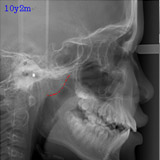

アデノイドの大きさについて

左はほぼ正常の状態で、わずかな腫れが認められますが問題ありません。

真ん中は軽度の腫れで、気道(空気の通り道)を少しふさいでいます。この場合は経過観察、または必要があれば耳鼻科で管理していただきます。

右は腫れが強く、気道をふさいでいます。この状態では鼻呼吸が困難であり、歯列、顔面発育にも影響がでる可能性が大きくなります。耳鼻科での治療を強くお勧めます。